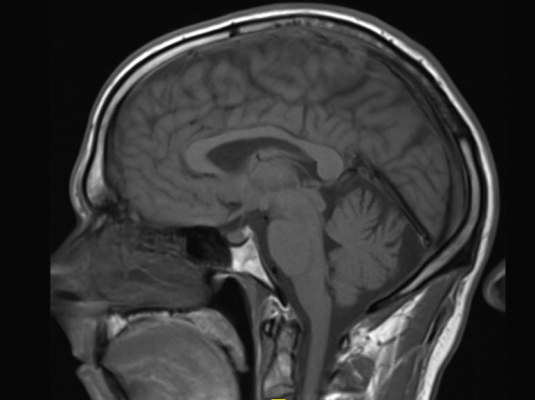

August 15, 2017 — The International Society for Magnetic Resonance in Medicine (ISMRM) has provided new guidance in the use of contrast agents during MRI scans. Emerging research suggests gadolinium-based contrast agents, injected in a patient's veins to brighten tissues in MRI images, accumulate in the brain. More than 300 million doses of such drugs have been administered since their introduction in 1987.

"Small amounts of gadolinium deposit in certain parts of the brain in people who undergo repeated gadolinium-based contrast agent enhanced exams," said Vikas Gulani, M.D., Ph.D., associate professor of radiology, urology and biomedical engineering at Case Western Reserve University School of Medicine, member of the Case Comprehensive Cancer Center, and director of magnetic resonance imaging at University Hospitals Cleveland Medical Center. "The ISMRM response is a review of the literature and a series of recommendations on what the community ought to do in response to this phenomenon." Gulani helped craft the new recommendations and served as first author for the review, featured on the cover of The Lancet Neurology.

In the review, Gulani and other experts suggest if gadolinium is not needed for a particular exam, it should not be administered. A risk-benefit analysis should happen for all exams. "Nearly everyone needs an MRI scan at some point, often contrast enhanced," Gulani said. "The idea that some gadolinium could be depositing in the brain is disconcerting to patients. In that situation, putting the risk and benefits into context is important." If gadolinium is needed, it should be administered and the choice of agent is dependent on a large number of factors, only one of which is the deposition phenomenon.

Defining harm is an important consideration. Gadolinium-based contrast agents have a proven track record for accurate diagnosis and treatment monitoring of a large number of diseases including cancer, neurological pathology, heart disease, liver disease, and many other important conditions afflicting adults and children. They are associated with few side effects, the most serious of which are extremely infrequent and affect already sick patients with severe kidney failure. The new review does not suggest sweeping changes in the use of MRI contrast agents, as at present, there is no evidence linking the brain deposits to health risks. However, it provides clarity about the previously unknown phenomenon of gadolinium deposition in the brain and provides guidance for future research.